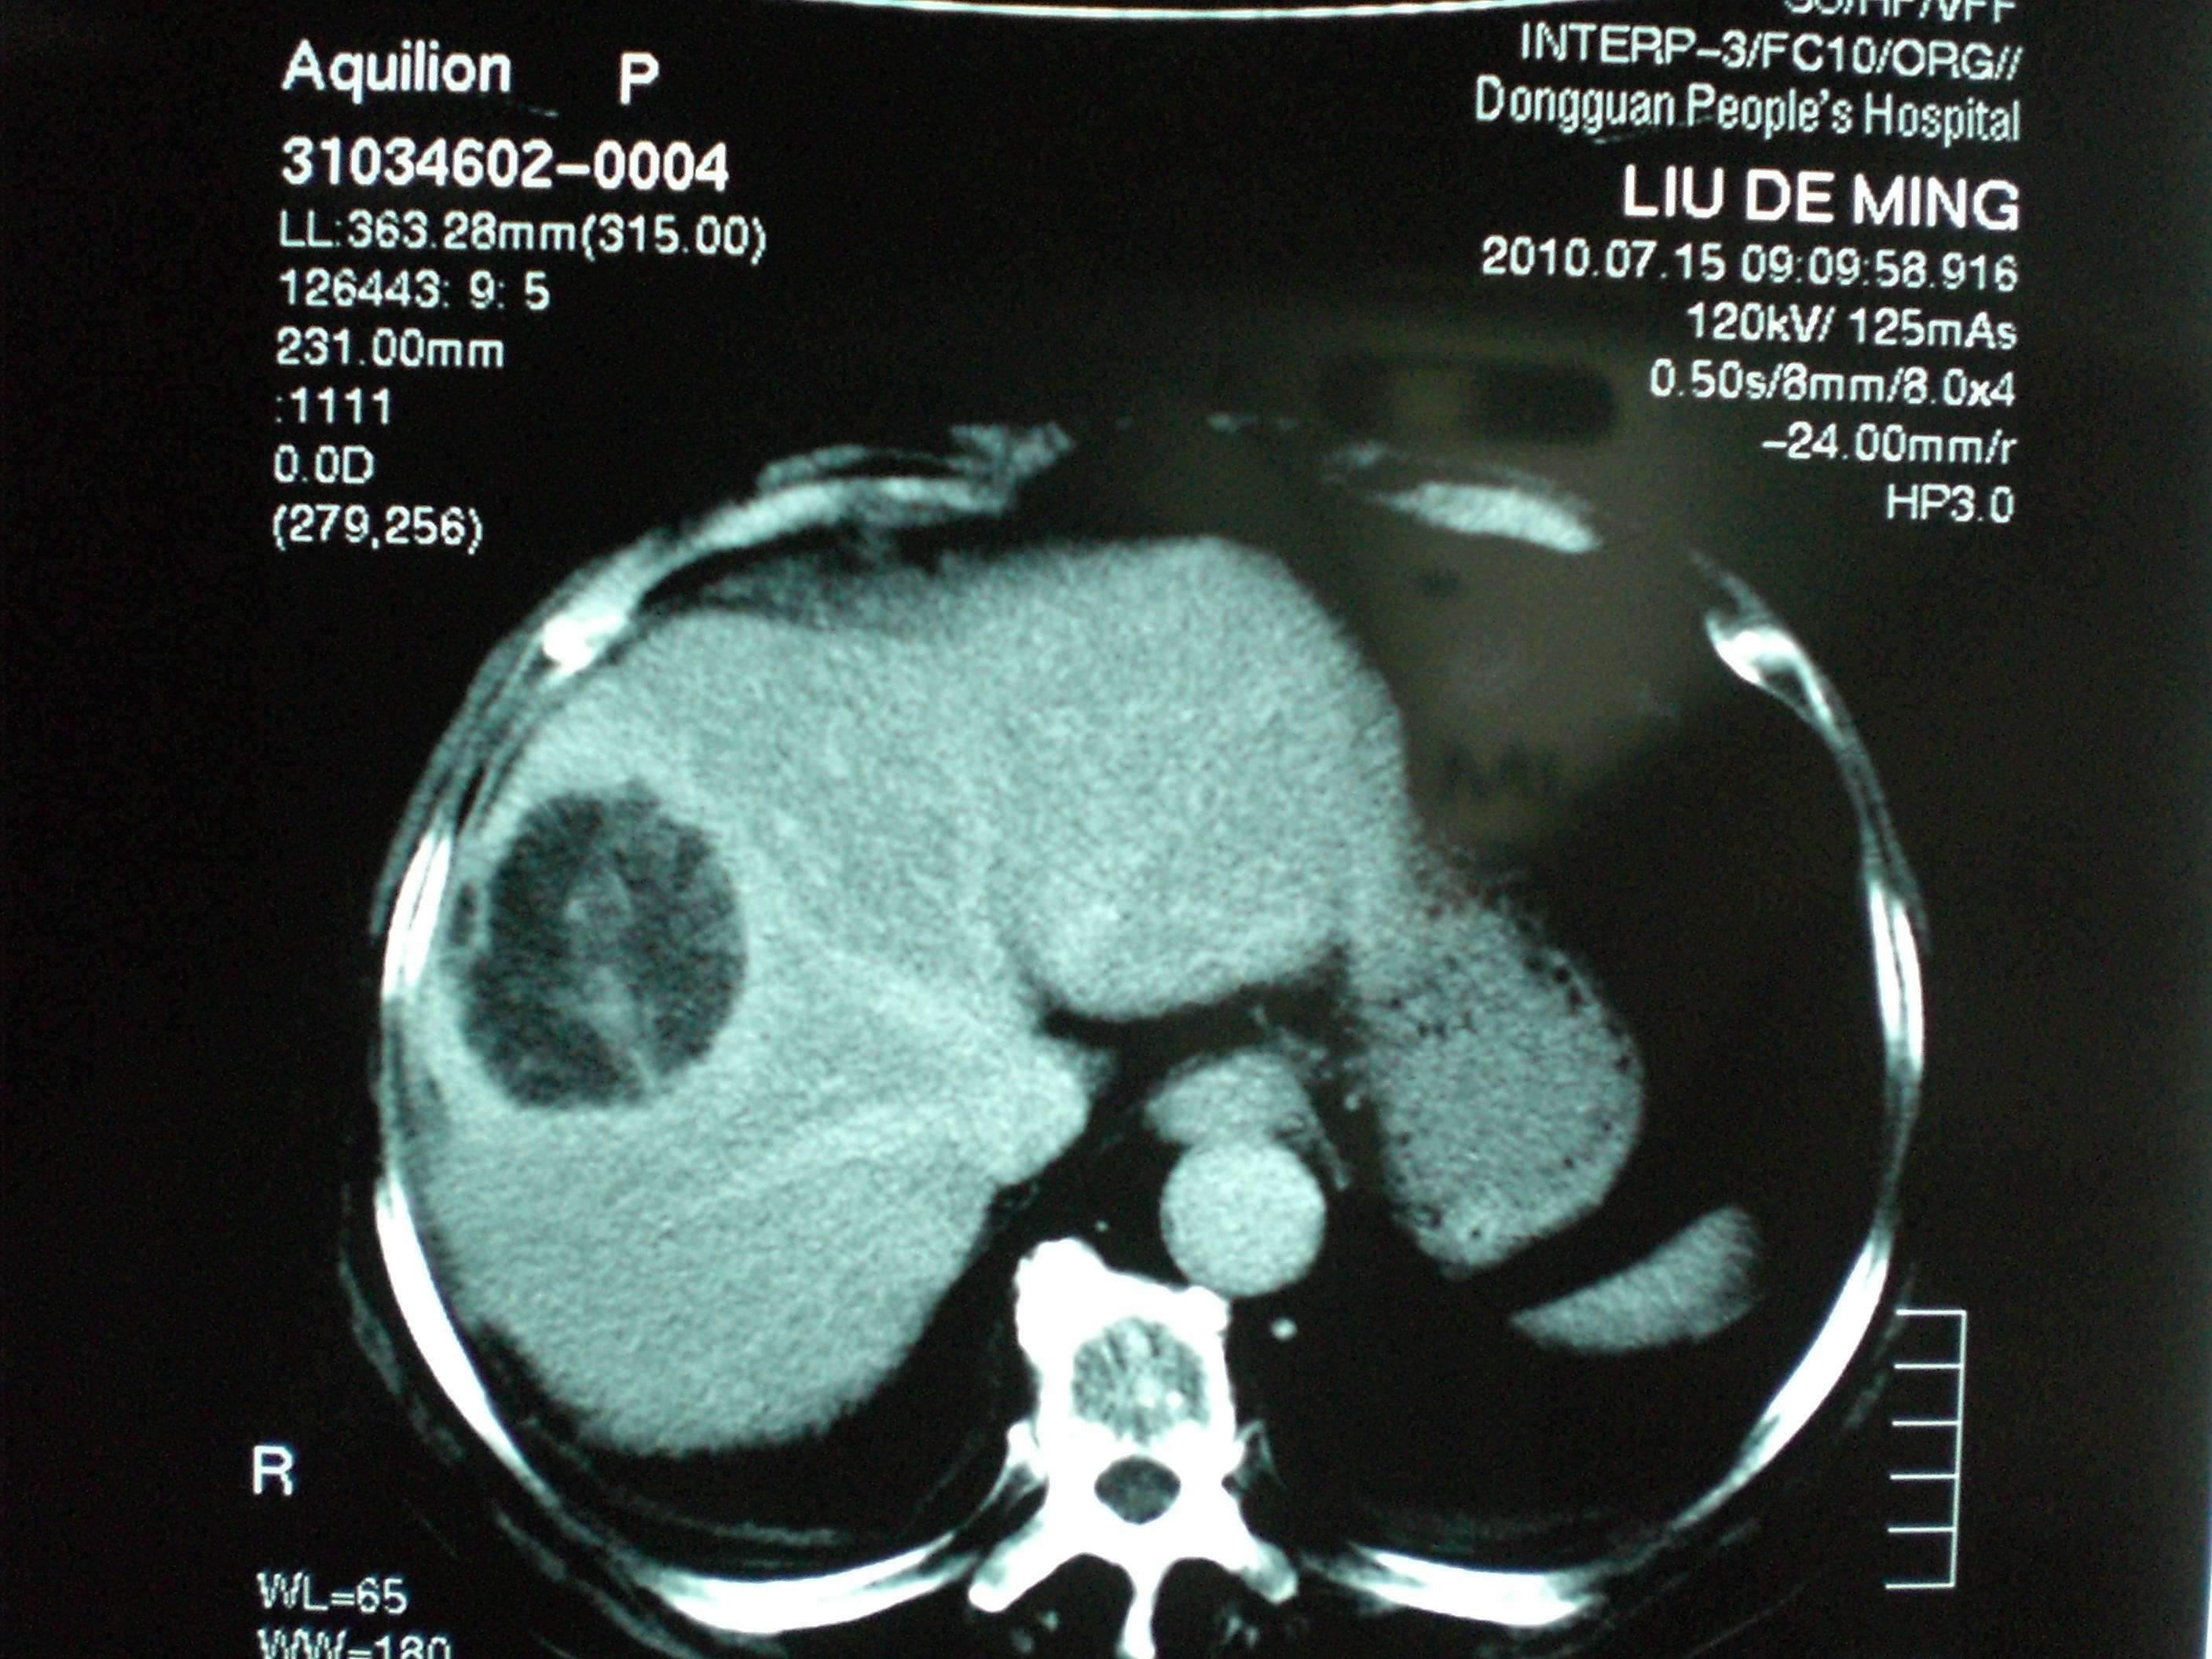

巨大肝癌

图片尺寸680x510